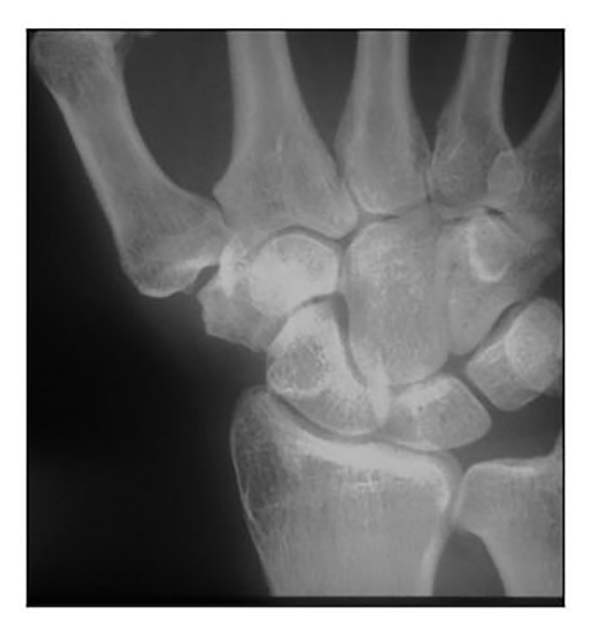

Die Rhizarthrose gehört zum rheumatischen Formenkreis und macht sich je nach Stadium durch eine sehr schmerzhafte zunehmende arthrotische Zerstörung des Daumensattelgelenkes bemerkbar. Nach einer Untersuchung von Pellegrini 1 erkranken Frauen 10- bis 15-mal häufiger an Rhizarthrose als Männer. Das deckt sich mit den Erfahrungen des Autors aus den Evaluierungsübersichten von fast 4.000 Patientinnen und Patienten mit dem durchschnittlichen Verhältnis von 13:1 zugunsten der Patientinnen. Die Rhizarthrose tritt bei Frauen nach den Erfahrungen des Autors ca. 3 Jahre nach dem Beginn der Menopause auf und ist vermutlich genetisch bedingt: Nur zwei Prozent der Patientinnen des Autors erwähnten in der Anamnese, keine Schwangerschaft gehabt zu haben. Auslöser für die Rhizarthrose bei Männern ist in den meisten Fällen eine traumatisch bedingte Verletzung des Daumensattelgelenkes („Skidaumen“) oder eine ständige berufliche Überbeanspruchung, zum Beispiel bei Vibrationen durch Maschinen oder auch durch handschriftliches Schreiben in Büroberufen. Die Rhizarthrose tritt nach Eaton/Littler radiologisch klassifiziert in vier Stadien auf (Abb. 1) 2:

- Stadium I: normale Gelenkkonturen, erweiterter Gelenkspalt (Erguss)

- Stadium II: geringe Gelenkspaltverschmälerung, evtl. vorhandene Gelenktrümmer kleiner als 2 mm

- Stadium III: sklerotische und zystische Veränderungen im subchondralen Knochen, Osteophyten größer als 2 mm, Zerstörung des Daumensattelgelenkes, normale trapezioskaphoidale Gelenkfläche

- Stadium IV: zusätzlich zum Verschleiß der trapeziometakarpalen Gelenkfläche degenerative Veränderungen im Bereich der trapezioskaphoidalen Gelenkfläche